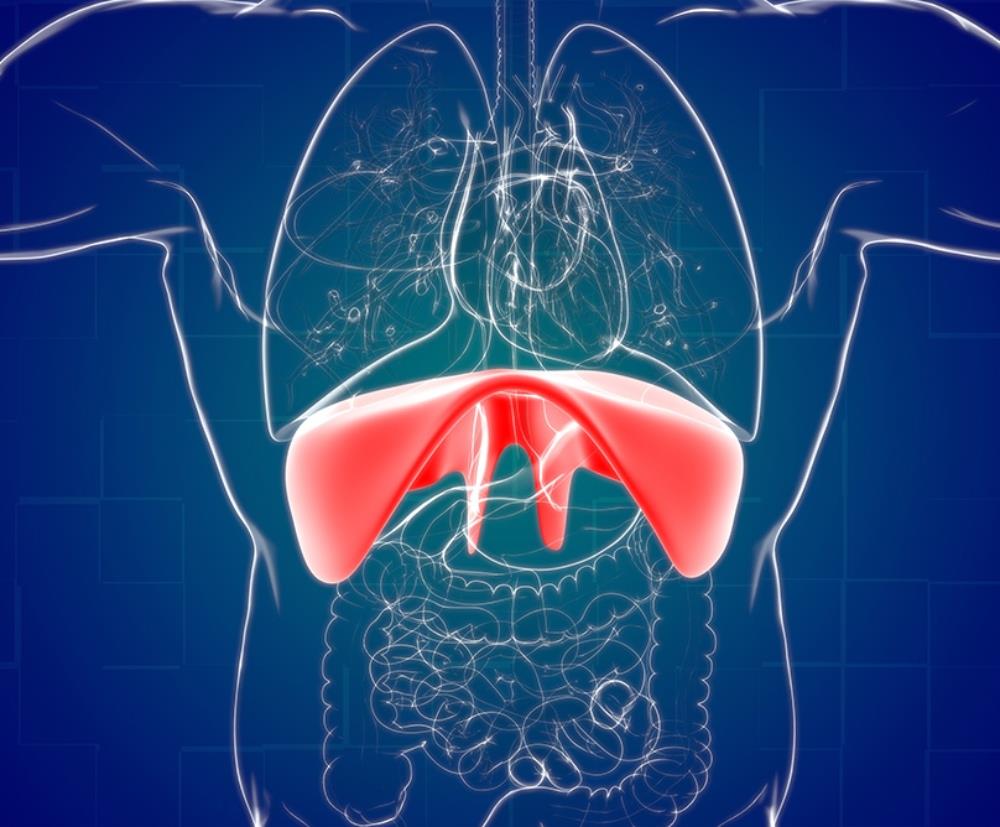

Η διαφραγματοκήλη διαφέρει από τις υπόλοιπες κήλες της κοιλιακής χώρας λόγω του ότι εμφανίζεται στο εσωτερικό της κοιλιάς. Πιο συγκεκριμένα, η διαφραγματοκήλη προκύπτει όταν δημιουργείται ένα κενό/χάσμα στο διάφραγμα, το μυ που χωρίζει την κοιλότητα του θώρακα από την κοιλιακή κοιλότητα, το οποίο επιτρέπει στα ενδοκοιλιακά σπλάχνα (στομάχι, έντερο, ήπαρ) να μετακινηθούν στη θωρακική κοιλότητα, προξενώντας μια σειρά από συμπτώματα και επιπλοκές για τον πάσχοντα.